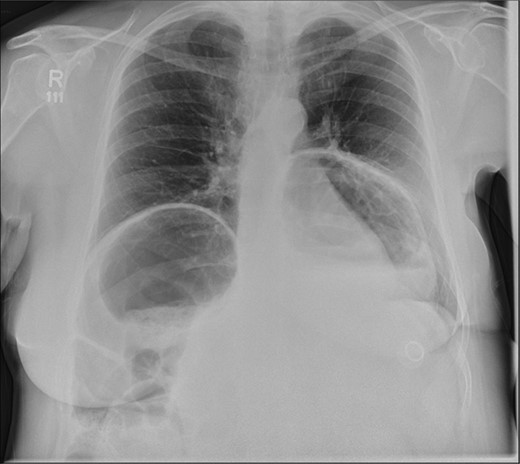

A 58-year-old female with a past medical history of a large intrathoracic hiatus hernia presented to her general practitioner and was subsequently referred to our surgical department with symptoms of sudden onset severe epigastric pain associated with vomiting and abdominal distension. Her abdomen was generally tender, maximally in the epigastric region, although she was not peritonitic. The admission erect chest radiograph showed a large hiatus hernia and an elevated right hemidiaphragm with a large loop of distended bowel (Fig. 1). Subsequent computed tomography (CT) scan demonstrated an almost completely intrathoracic stomach with a degree of volvulus, and the liver medially displaced by a loop of large bowel felt to be caecum (Fig. 2). Since the patient remained otherwise well, bidirectional endoscopy was performed, and given that a volvulus point could not be identified and the ileocaecal junction was not identified, contrast studies were requested (Figs 3–5) which demonstrated an incomplete obstruction caused by a volved caecum rotated anteriorly and cephalad.

Erect chest radiograph, showing a large hiatus hernia and large loop of bowel elevating the right hemidiaphragm.